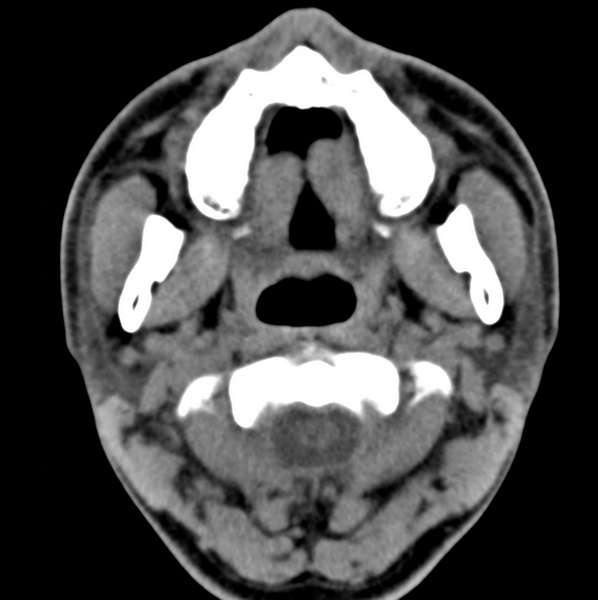

男、31、鼻咽部肿瘤放疗后请帮忙看看。

效果好,右侧破裂孔扩大,局部骨质缺损,为颅底骨质破坏。

1)鼻咽部肿瘤侵犯颅底放疗术后改变。2)左侧蝶窦炎。

咽后壁增厚,左侧咽鼓管隆突增大、咽鼓管咽口变浅,同侧咽旁间隙较窄。右侧颅底骨质破坏?为什么不在同一侧?

鼻咽部肿瘤侵犯颅底放疗术后改变.